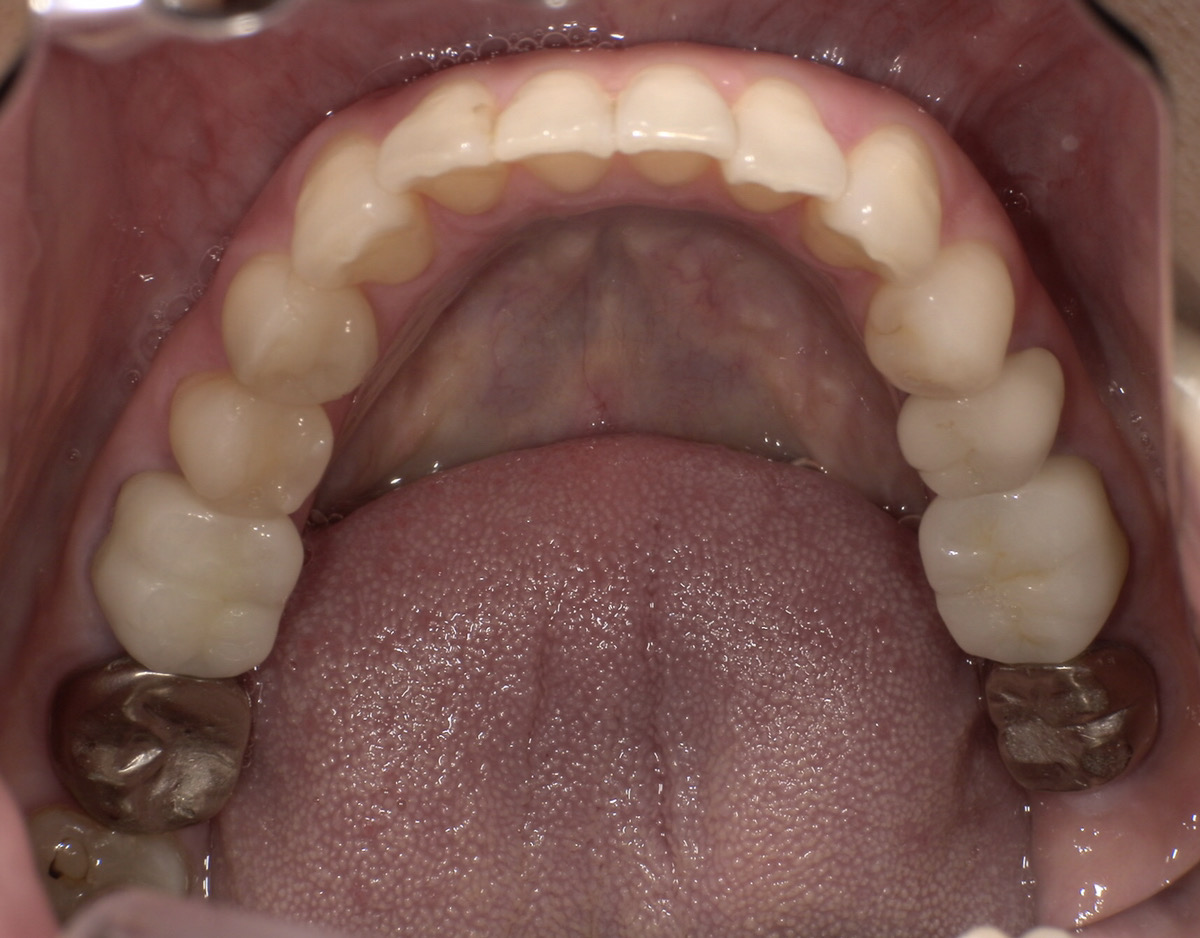

CASE 02

Before

After

施術内容下の銀歯を白くしたいとのこと。下顎左右第一大臼歯の銀歯をジルコニアクラウンに交換。

治療期間2か月

リスク・副作用ジルコニアは非常に強度が高いですが、強い衝撃や極端に強い噛み合わせ、歯ぎしり・食いしばりなどがある場合、まれに割れたり欠けたりする可能性があります。

費用198,000円

※表示金額は全て税込みです。